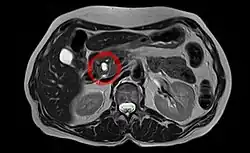

Zystisches Adenokarzinom in der CT (Tumor rot, Pankreas grün markiert)

Unspezifische Symptome wie Missempfindungen/Druck im Oberbauch, Appetitlosigkeit, Übelkeit, Verdauungsprobleme und depressive Verstimmungen können erste Anzeichen des Pankreaskopfkarzinoms sein. Später zeigt sich häufig das Leitsymptom des Pankreaskopfkarzinoms, eine zunehmende, nicht von Koliken begleitete Gelbsucht (Ikterus),[33] die durch die Verengung des Gallengangs verursacht wird. Diese Gelbsucht ist nur bei Papillentumoren ein Frühsymptom, ansonsten Zeichen eines fortgeschrittenen Befundes. In den Rücken ausstrahlende Bauchschmerzen (u. a. gürtelförmig ausstrahlende Schmerzen im mittleren Rückenbereich) sind ebenfalls häufig, aber uncharakteristisch. Allerdings sind die quälenden, über Monate langsam zunehmenden dumpfen, nachts verschlimmerten Schmerzen, die durch Infiltration des Sonnengeflechtes entstehen, oft der erste Anlass, einen Arzt aufzusuchen. Ein Courvoisier-Zeichen (prall tastbare Gallenblase) ist möglich. Verengungen des Pankreasgangs beeinträchtigen die Drüsenfunktion und verursachen Verdauungsbeschwerden, Gewichtsverlust um mehr als 10 % und Diabetes (u. a. plötzlich auftretend). Weitere Anzeichen können Durchfall und Fettstühle (lehmartig, hell) sein. Thrombosen (u. a. Beinvenenthrombose) und neue Pigmentierungen der Haut sind Warnhinweise auf einen Tumor im Bauchraum. Im späten Erkrankungsstadium können Metastasen zur Lebervergrößerung, Leberfunktionsstörung, Bauchwassersucht und hochgradiger Abmagerung führen.